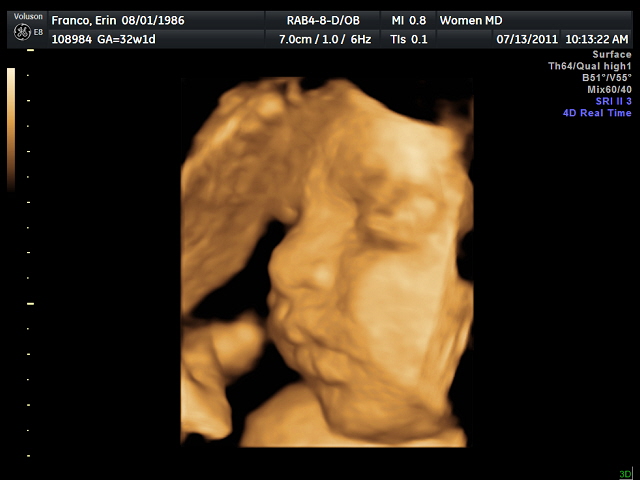

This is a picture of Gabriel when he was less than a week old. I can’t believe I’m having another one of these in just a few weeks!

I’m looking so forward to meeting my baby girl! πŸ™‚